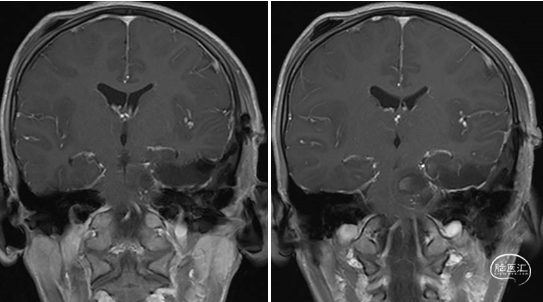

术前MRI

术后MRI